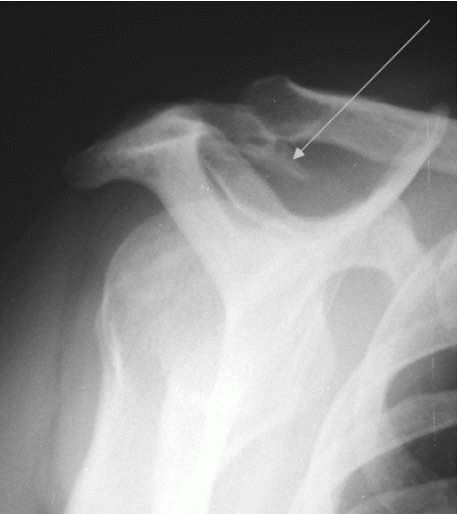

may be evident on radiographs. Certain specialized views, including the

supraspinatus outlet (Figure 12-30) (10 to 15°

caudal tilt lateral scapular view) and Zanca (10 to 15° cephalic tilt

AP coronal view), may also be obtained to look specifically for outlet

narrowing and AC joint degeneration.